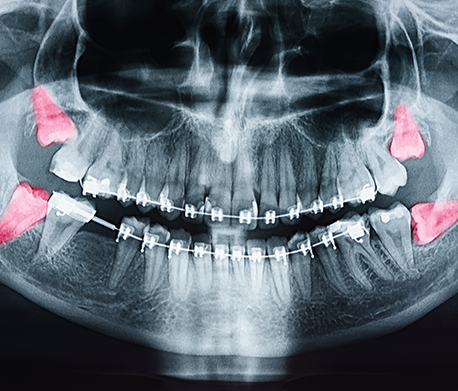

Every person has four wisdom teeth in their mouth, but very few people keep their wisdom teeth through adulthood. Typically, the average person’s mouth is not large enough to accommodate wisdom teeth because they grow in at an angle.

Wisdom teeth can start coming into a person’s mouth during their late teenage years or at any time afterwards. Sometimes, all four wisdom teeth will begin pushing through at once, which is when severe discomfort can occur. Because wisdom teeth come in at an angle, they will push against the teeth next to them. The pain that results from their arrival can be almost debilitating, with many people facing difficulties and discomfort when opening or closing their mouth.